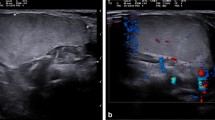

Lipoblastoma with septations in a boy age 1 year 7 months with growing thigh mass and restricted flexion. a Sagittal post-contrast T1-weighted fat-saturated MR image of the knee shows a complex fat-containing mass in the deep popliteal fossa with moderate enhancement of the marked septations within this lesion. (In an adult, these imaging features would suggest the diagnosis of a well-differentiated or myxoid liposarcoma.) b Gray-scale US image shows a predominantly hyperechoic lesion with interspersed hypoechoic septations (arrowheads). c Histopathology (hematoxylin and eosin stain, 40x magnification) shows predominantly fat-containing mass in keeping with lipoblastoma with septations (arrowheads) and myxoid areas (asterisks)

Ultrasound imaging features

All of the lesions imaged with US in this study were hyperechoic with septations (Fig. 1). US demonstrated relatively limited utility for invasive manifestations of lipoblastoma because deeper components could not be well-assessed due to technical limits of sonographic penetration. We performed no additional analysis of US data because of the limited nature of US images available in this database.